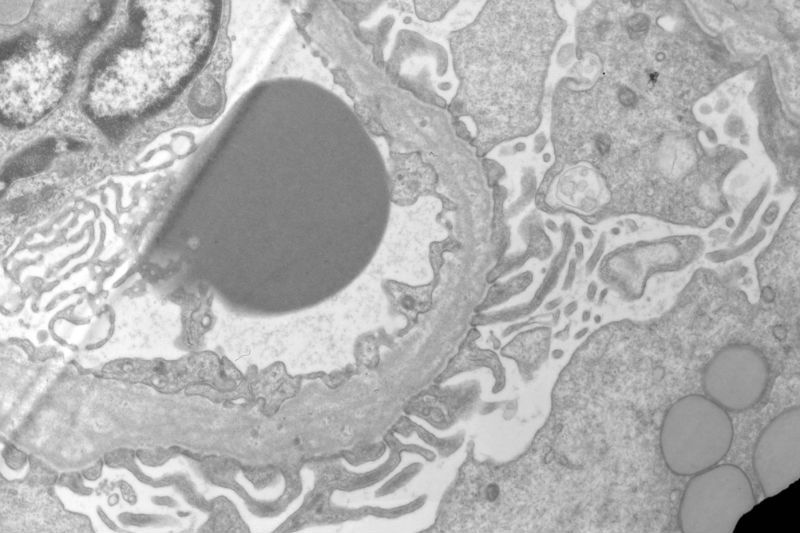

Sixty old man with proteinuria and hematuria

• Sixty old man with proteinuria and hematuria图2

图2

Picture 2 you fisrt posting showed a lot of foamy cells and some things like HP  in a tubular cavity in the centre of picture. About picture 7, i can see one capillary loop and its endothelial cell, i'm doute of  like a tadpole someting different in the capillary cavity , can you tell me, thank you very much.

In the photo #7, there are three platelets in the capillary lumen. I don't know their significance.

Thank you,to combine the splitting of the glomerular basement membrane with a lot of foamy cells infiltration, I first take into account Alport Syndrome, but the age of the patient is too old, so Alport Syndrome seems unlikely. Under LM, the glomerulosclerosis and tubular atrophy/interstitial fibrosis. Please comment, thank you

The patient has a long history of "chronic kidney disease". Initially, he did not tell the nephrologist that he started to have kidney disease decades ago. Given the characteristic ultrastructural changes, Alport's syndrome is suggested.